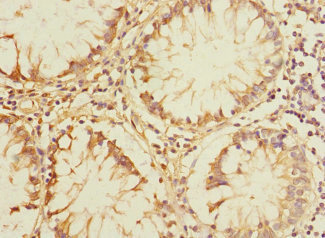

PLK3 Antibody

產品名稱:Rabbit anti-Homo sapiens (Human) PLK3 Polyclonal antibody

免疫原:Recombinant Human Serine/threonine-protein kinase PLK3 protein (487-646AA)

應用范圍:ELISA, IHC

Application Recommended Dilution IHC 1:20-1:200 -